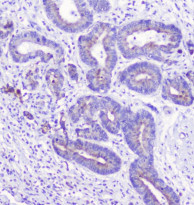

ARG43046 anti-LATS1 / WARTS antibody IHC-P image

Immunohistochemistry: Paraffin-embedded Human placenta tissue. Antigen Retrieval: Heat mediation was performed in Citrate buffer (pH 6.0) for 20 min. The tissue section was blocked with 10% goat serum. The tissue section was then stained with ARG43046 anti-LATS1 / WARTS antibody at 1 µg/ml dilution, overnight at 4°C.